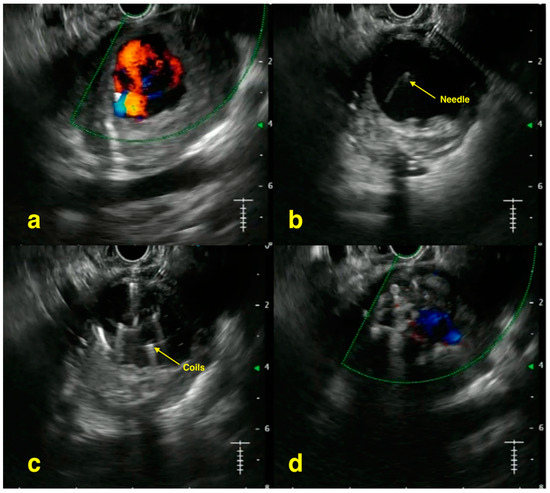

- Chavan, R.; Baraldo, S.; Patel, N.; Gandhi, C.; Rajput, S. Technical tips for EUS-guided embolization of varices and pseudoaneurysms. VideoGIE 2023, 9, 211–219. [Google Scholar] [CrossRef] [PubMed] [PubMed Central]